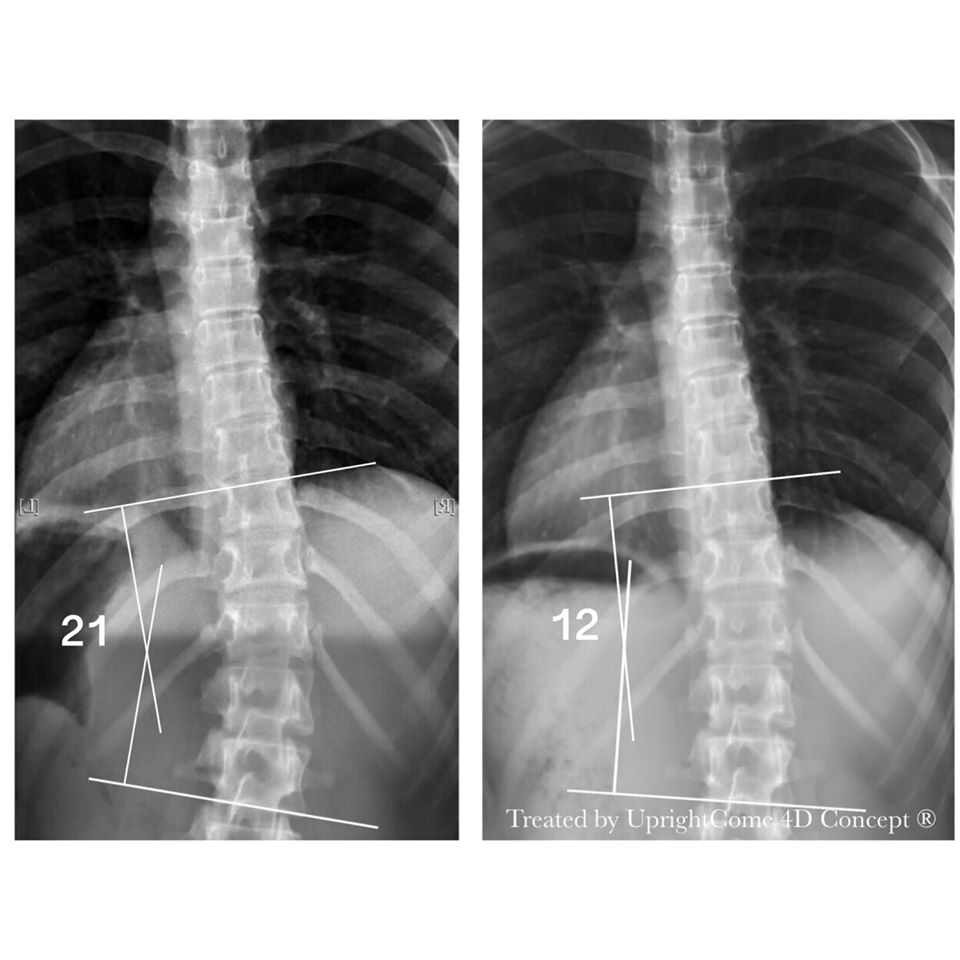

Let the Numbers Speak!

2020-01-02The 16-year-old girl and her mother finally smile. The thoracic curve is improved from ...